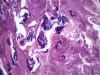

Опухоль матки |

Плоскоклеточный умереннодифференцированный рак,инвазия в железы.